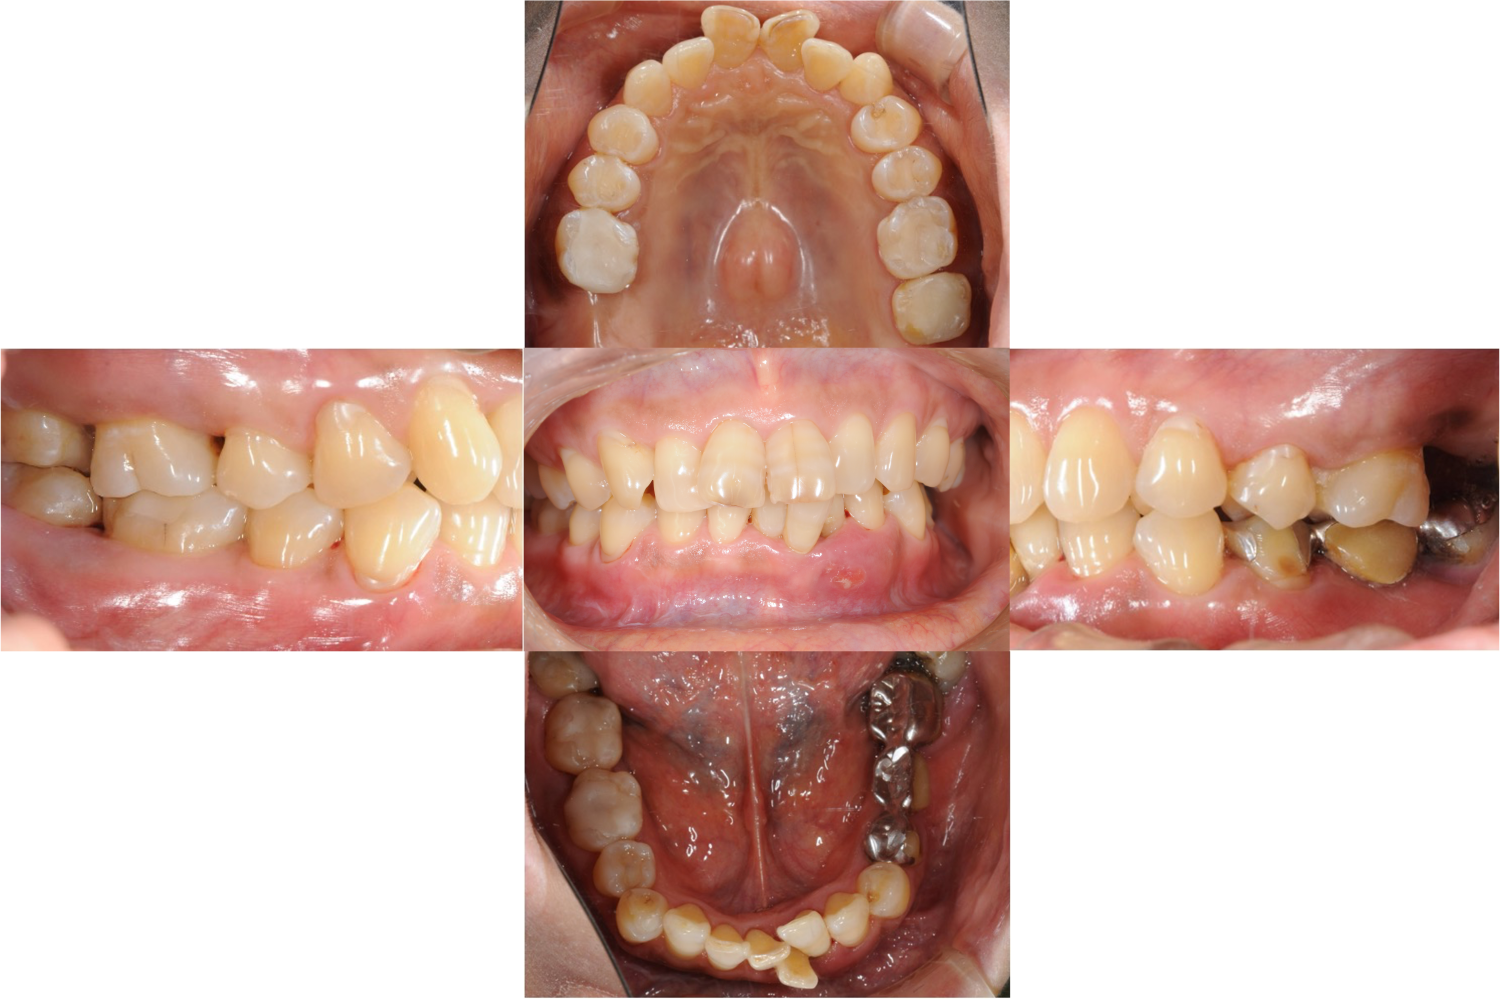

歯周病に罹患した患者さんのインプラント治療の症例②(うえだ歯科)

上田大介(うえだ歯科)

症例詳細

| 主訴 | 全顎治療希望、全顎的に歯が動く、奥の歯がなくて噛めない。できるだけ綺麗で噛めるようになりたい。 |

| 治療内容 | 全顎的に歯周病、前歯部の被蓋が深く、重度歯列不正が認められるため、 歯周外科を含む歯周治療、矯正治療、インプラント治療、セラミックによる補綴治療後メインテナンスに移行しました。 |

| 治療費 | 5,060,000円(税込)(インプラントすべて含む) |

| 治療期間 | 2年4ヶ月 |

| 治療回数 | 90回 |

| 想定されたリスク | 矯正治療の後戻り、歯周病の再発、食いしばり(パラファンクション)によるセラミックの破折、歯の破折のリスクがありました。 |